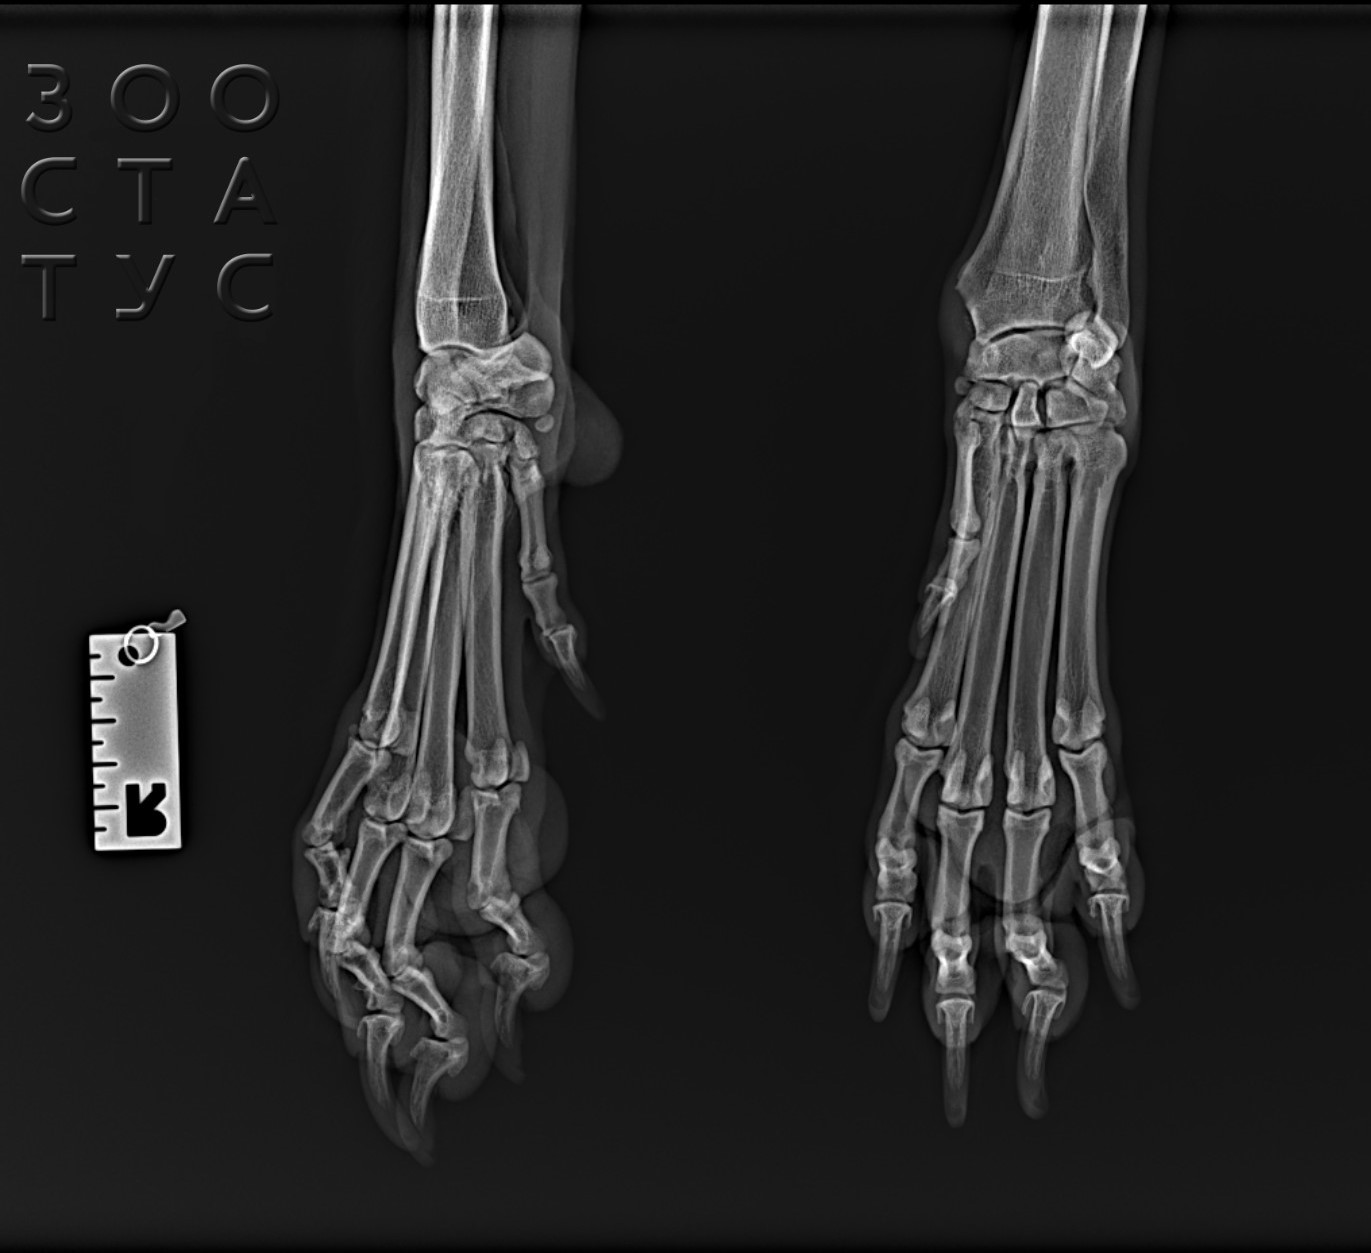

- после автотравм, падения с высоты - рентген позволяет не только выявить переломы конечностей у кошки, но и обследовать грудную клетку, вовремя выявив жизнеугрожающие травмы;

- рентген лап обязательно нужен при любых других травмах, проблемах с опорно-двигательным аппаратом, хромотой, вялости (кошки хорошо могут скрывать болезненные ощущения после ушибов или растяжений, просто начинают меньше двигаться);

Практически всегда для ортопедического обследования (травмы, хромота) седация необходима, так как иначе невозможно будет расположить сустав в нужной проекции - животное будет дергаться, выворачиваться, и данные исследования могут быть значительно искажены. Также рентген для кошек проводится под седацией для агрессивных, сильно напуганных кошек, с которыми владелец не может справиться.